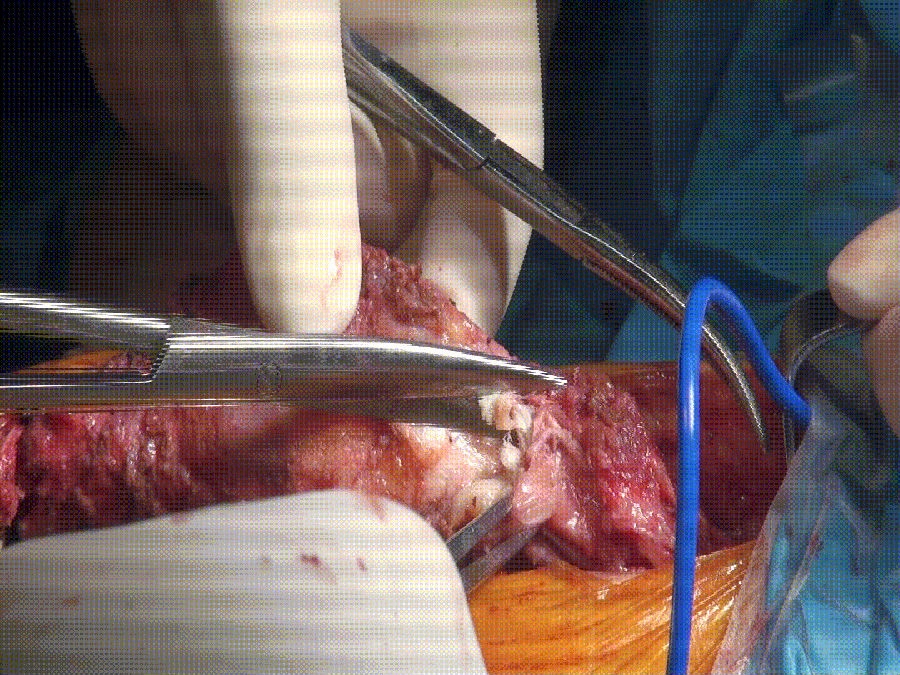

术中因骨质疏松,发生外侧副韧带止点撕脱性骨折。采用强生带线锚钉固定。

锚钉固定 撕脱性骨块